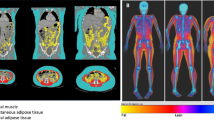

Three-thousand two-hundred thirty-one children (mean age 10.2 (range 8.6–12.9) years) were evaluated with MRI of the hips, pelvis, and lumbar spine, as part of a prospective population-based pediatric cohort study. Scans were reviewed by trained medical staff for abnormalities. IFs were categorized by clinical relevance and need for further clinical evaluation.

8.3% (n = 267) of children featured at least one IF. One or more musculoskeletal IFs were found in 7.9% (n = 254) of children, however, only 0.8% (n = 2) of musculoskeletal IFs required clinical evaluation. Most frequent abnormalities were simple bone cysts 6.0% (n = 195), chondroid lesions 0.6% (n = 20), and perineural cysts 0.5% (n = 15). Intra-abdominal IFs were detected in 0.5% (n = 17) of children, with over half (n = 9) of these requiring evaluation. The three most common intra-abdominal IFs were a duplex collecting system 0.09% (n = 3), significant ascites 0.06% (n = 2), and hydroureteronephrosis 0.06% (n = 2).